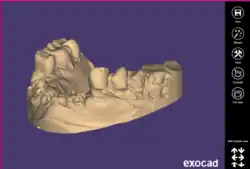

The initial stage commences with the acquisition of 3D representations of the patient's jaw by merging digital data from CBCT scans with optical data gathered from an intraoral scanner. Various software platforms excel in handling this data, spanning from converting CBCT images into 3D files to creating prosthetic models. Leading software choices for these processes include Dental Wings, Shape 3D and Exocad. Additionally, documenting the soft tissue state and existing teeth is crucial, accomplished through photographic records.